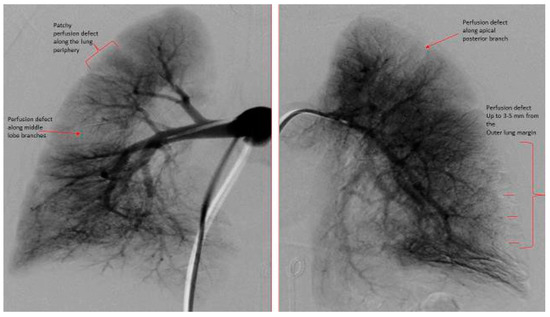

| Digital subtraction pulmonary angiogram: | |||

| Pulmonary Vascular Underperfusion Score (PVUS) a (mean ± SD) | 2.66 ± 0.47 | 5 ± 0.81 | 0.0048 |